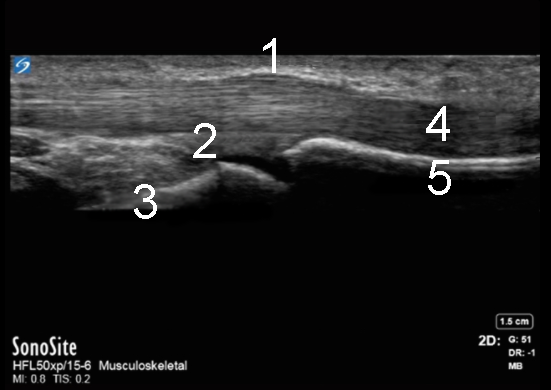

Hand A1 Pulley Transverse Image

1. A1 Pulley

2. Volar Plate

3. Distal Metacarpal Head

4. Flexor Tendon

5. Proximal Phalanx